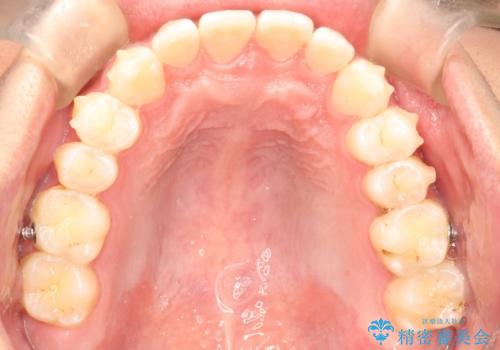

前歯がガタガタ インビザラインによる矯正

- 前歯がガタガタ、下の犬歯が飛び出ているのを主訴に来院されました。

下の奥歯を後方へ移動させてスペースを確保して、前歯を並べる計画としました。

目立たない装置をご希望されたので、インビザラインにて矯正治療を行いました。

使用時間を守っていただけたので、比較的スムーズに矯正を終了することができました。